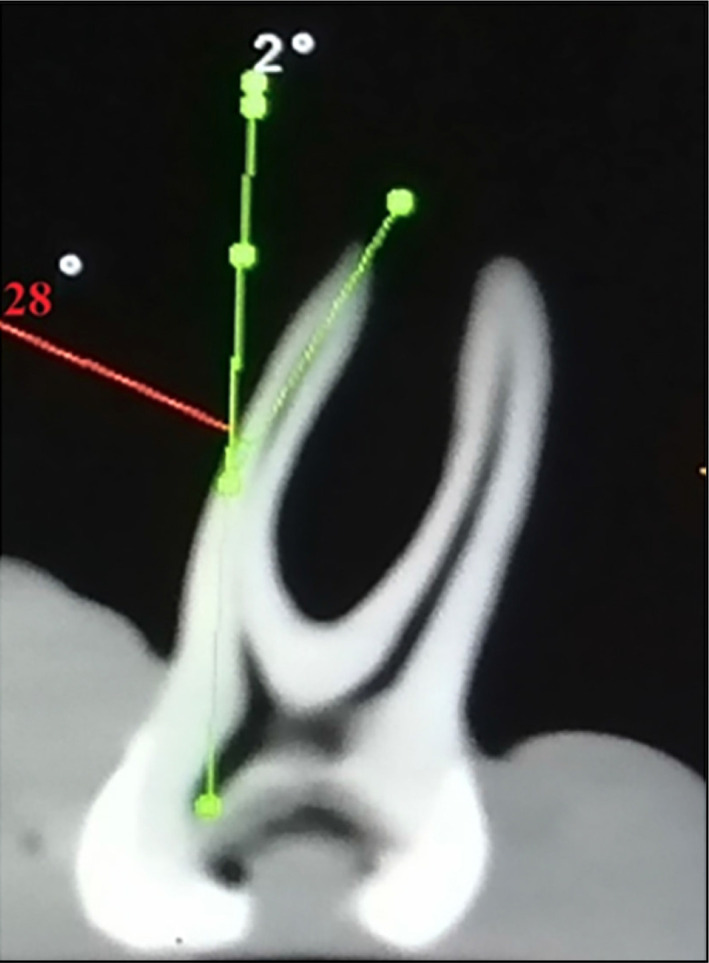

Methods: In this study, 40 extracted mandibular first molar roots were selected and divided randomly into four groups (n=10). Group MWOG: a manual glide path was performed + WOG primary. Group MTRN: manual glide path performed+TRN prime. Additionally, group WOGG: glide path preparation with WOGG+WOG primary. Finally, for group TRNG, the glide path preparation was performed with TRNG+TRN prime. Micro-CT was used for pre and post-instrumentation image analysis. Statistical analysis was performed using the Kruskal- Wallis test (p<0.05) with Two-way ANOVA.

Results: The Kruskal-Wallis test showed no significant differences among all groups in all thirds for pre and post-instrumentation regarding the crack formation. The Two-way ANOVA showed no significant difference or interaction between the ways of glide path preparation, whether manual or reciprocal WOGG, or between the rotary TRNG and the motion used in root canal preparation (rotary TRN or reciprocal WOG) regarding the crack formation and propagation.

Conclusion: Microcrack formation and propagation occurred independently of using different glide path techniques (manual, rotary, or reciprocal).